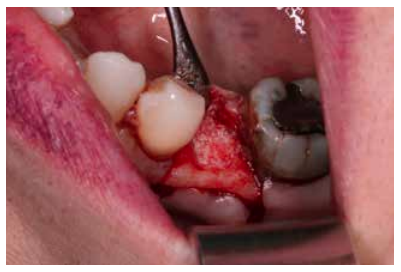

Materials and methods: A study was carried out on 6 patients from the Faculty of Dentistry of the Complutense University of Madrid performing the technique of alveolar ridge preservation. Two groups were established, a test group in which the alveolar socket was filled with calcium phosphate and added silicon and a control group where the socket was filled with bovine hydroxyapatite. After 3 months, a cone-beam computed tomography was performed to evaluate the bone density achieved by both biomaterials.

Andrés-Veiga et al,7 observed that this amount of bone resorption can vary between one individual and another and even in the same individual at different times of life, due to the influence of a series of local and systemic factors. Post-extraction alveolar ridge preservation (PAP) is a surgical technique aimed at reducing the collapse of the alveolar ridge after tooth extraction with a biomaterial, to facilitate subsequent implant rehabilitation8-10.